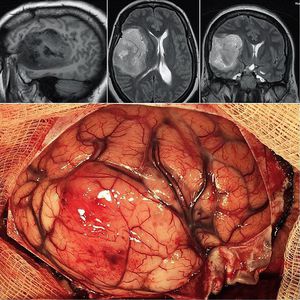

Neurosurgery dose of the day! Here's a glioblastoma multiforme (grade IV astrocytoma) from the right temporal lobe in a 56 years old female patient. This kind of tumor is the most common and most aggressive malignant brain tumor, it arises from astrocytes—the star-shaped cells that make up the “glue-like,” or supportive tissue of the brain and are highly malignant (cancerous) because the cells reproduce quickly and they are supported by a large network of blood vessels. The top images from the left shows T1 sagittal, T2 axial, and T2 coronal weighted MRI. The patient presented with progressive headache, left hemiparesis (remember right hemisphere has a control over the left body), and hyposthesia (reduce sense of touch). You may also notice the difference in the color and vessels from the healthy brain. Treatment typically involves chemotherapy, radiation and surgery. Credit : @rpaglioli